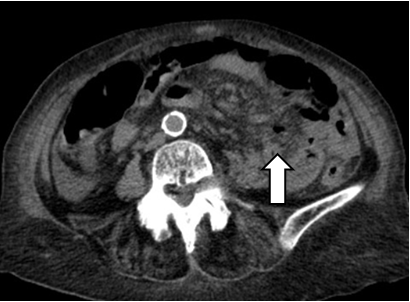

101-year-old female without history of gastrointestinal symptoms, debuted with periumbilical abdominal pain and generalization of pain, accompanied by nausea, headache, and diarrhea for 4 days. Physical examination showed hypotension and tachycardia, chills, asthenia, adynamia, intense abdominal pain, tenderness, and stiffness. Laboratory tests showed diminished white blood cell count (3.07x109uL), procalcitonin level elevation, metabolic acidosis, and elevated lactate. Abdominal CT scan revealed pneumoperitoneum, free abdominal fluid and whirlpool sign at jejunum (Figure 1 & 2). Exploratory laparotomy was performed, finding 1000 ml of intestinal fluid, jejunal diverticulum of 6x4 cm, 50 cm distant from the Treitz angle, with perforation of 1 cm (Figure 3), and multiple distal diverticula. She was managed with intestinal resection and anastomosis. She was discharged from the hospital 7 days after the surgery. Diagnosis was confirmed by pathology report (Figure 4 & 5).

Figure 2 CT scan, axial cut, evidencing the whirlpool sign.